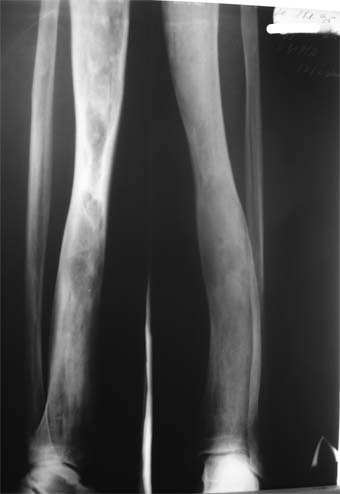

Эти жалобы беспокоят втечение 5-6 лет. В 1999 году выявили "изменения" (со слов больного, выписки нет на руках) бедренной кости и костей голени слева. Тогда же предложили в ЦИТО срочно делать какую-то операцию.

Голень обычной формы. Объем движений в суставах полный. Кровоснабжение, иннервация сохранены. Имеется разница в длине конечностей правая короче на 4-5 см за счет бедра и голени.

В приложении вид больного и рентгенограммы бедра 2001 год и 2005 год.

2001

В настоящее время имеется умеренный рубцовый процесс правого бедра не мешающий на объем движений в суставах. В коленном суставе слева бедро обычное, голень - булавовидное утолщение проксимального конца большеберцовой кости. На рентгенограммах тотальное поражение кости с увлечением в процесс проксимального эпиметафиза, поражение характерно для болезни Campanatsehi

У больного полиоссальноая форма фиброзной дисплазии с поражение левой бедренной и большеберцовой кости. На рентгенограммах - тотальное разрастание и остончение кортикального слоя. Имеется удлинение левой нижней конечности на 2,5-3 см за счет голени. Больному показано оперативное лечение левой большеберцовой кости.